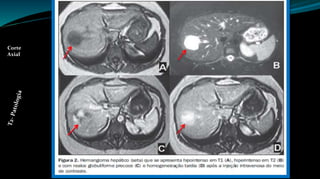

Imagem Patológica (Hemangioma)

Fase Arterial Fase Portal Fase Tardia

Fonte: GOOGLE, 2014

Corte

Axial

T2- Patologia

Imagem Patológica (Hemangioma) Fase Arterial Fase Portal Fase Tardia Fonte: GOOGLE, 2014 Corte Axial